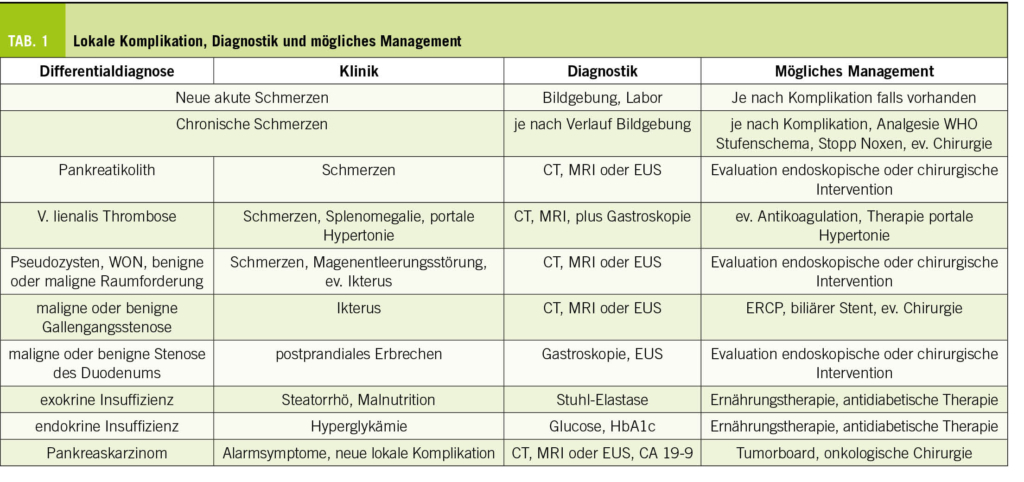

Das Risiko für ein Adenokarzinom des Pankreas (Abb. 1) als schwerwiegendste Komplikation und Differentialdiagnose ist deutlich erhöht (4). Beispielsweise fünf Jahre nach Diagnosestellung der chronischen Pankreatitis ist das Karzinomrisiko achtfach erhöht (5). Ein Pankreaskarzinom Screening ist ausser bei der hereditären chronischen Pankreatitis oder positiven Familienanamnese für Pankreaskarzinom jedoch nicht empfohlen (6). Treten B-Symptome, Ikterus oder eine neue exo- oder endokrine Insuffizienz auf, sollte aktiv mittels Schichtbildgebung ein Karzinom gesucht werden.

Weitere wichtige lokale Komplikationen sind in der Tabelle 1 zusammengefasst.